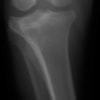

術前左後肢側面像

術前正面像

手術前後のTPA(脛骨高平部の角度)を測定しています。

約29°から約10°へ矯正されています。

術前のTPAは左後肢33.1°右後肢26.8°でしたがTPLO実施により左後肢5.5°右後肢12°に矯正されました。